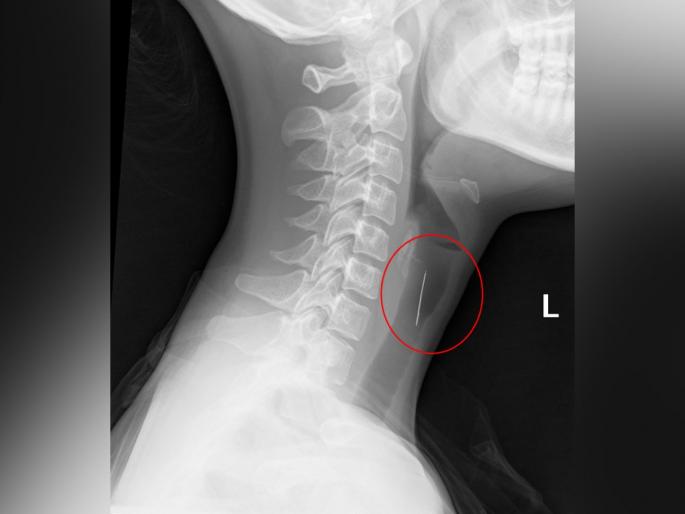

महिलेच्या काही प्राथमिक तपासण्या केल्यानंतर डॉक्टरांनी लगेचच तिच्या घशाचा एक्स-रे केला. एक्स-रेमध्ये जे समोर आलं त्यामुळे अनेकजण हैराण झाले. डॉक्टरांनी महिलेकडे तिने काय खालं होतं याची चौकशी केली तेव्हा महिलेने आपण स्ट्रॉबेरी खाल्याचे त्यांना सांगितले. खरं तर महिलेने स्ट्रॉबेरीसोबतच एक सुई गिळली होती. तिच सुई महिलेच्या घशात अडकली असून त्यामुळेच तिला घशामध्ये असह्य वेदना होत होत्या.

मीडिया रिपोर्ट्सनुसार, स्काईच्या वडिलांनी घडलेल्या घटनेबाबत बोलताना सांगितले की, त्यांच्या मुलीला स्ट्रॉबेरी खाल्यानंतर हॉस्पिटलमध्ये दाखल करण्यात आलं. त्यांनी सांगितलं की, स्ट्रॉबेरीच्या आतमध्ये सुई होती. मुलीने नकळत स्ट्रॉहेरीसोबत सुईही खाल्ली. जेव्हा तिला याबाबत समजलं तेव्हा ती हैराण झाली. आम्ही तत्काळ तिला हॉस्पिटलमध्ये दाखल केलं. तेव्हा डॉक्टरांनी तिचा एक्स-रे केला आणि त्यामध्ये घशामध्ये सुई अडकल्याचे दिसून आलं.'